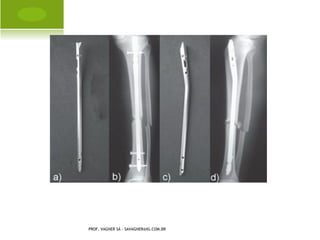

SUBTROCANTÉRICA

PROF. VAGNER SÁ - SAVAGNER@IG.COM.BR

DIÁFISE